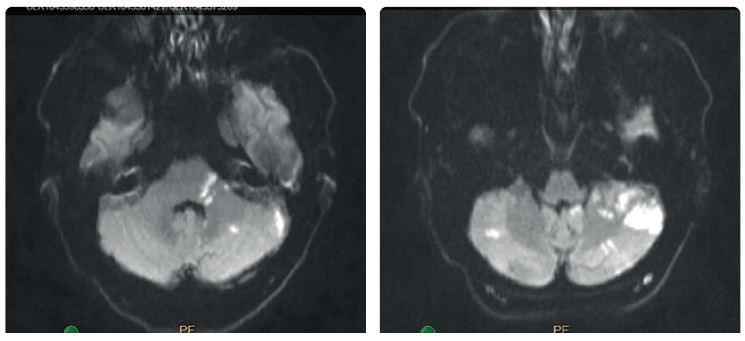

Na zobrazení MR DW (MR obraz s difuzním vážením) byly patrné čerstvé ischemické změny v dolní části levé mozečkové hemisféry v teritoriu PICA (arteria cerebelli inferior posterior) vlevo, a dále v bazi levého brachium pontis. Drobné změny jsou i v teritoriu horní mozečkové tepny vlevo a drobný okrsek restrikce MR DW v dolním okraji pravé mozečkové hemisféry v teritoriu PICA vpravo (obr. 1). Na CTA (výpočetní tomografie – angiografie) a DSA (digitální subtrakční angiografie) byl patrný uzávěr odstupu obou vertebrálních arterií (obr. 2). Zadní mozkové řečiště, tzn. bazilární tepna (BA), PCA a distální části vertebrálních tepen, se plnilo retrográdně cestou zadních komunikant (obr. 3). Retrográdní tok v levé a. vertebralis dosahoval až do extrakraniálního úseku V3 v oblasti oblouku prvního krčního obratle C1 (obr. 4). Nová vyšetřovací modalita QMRA prokázala retrográdní tok v levé zadní komunikantě 30 ml/min a sotva detekovatelný retrográdní tok v bazilární arterii 17 ml/min (obr. 5).

Na kontrolním vyšetření CTA je patrný bypass z povodí arteria carotis externa cestou a. occipitalis na vertebrální arterii (obr. 8A–B). Pooperační vyšetření QMRA ukazuje obnovený antegrádní tok v levé a. vertebralis 60 ml/min, antegrádní tok v a. bazilaris a fyziologický průtok v PCA. Pacient dochází na pravidelné ambulantní kontroly, jeho stav je stabilizovaný, v neurologickém obraze přetrvává jádrová paréza lícního nervu a ischemická mozková příhoda z VB povodí se neopakovala.